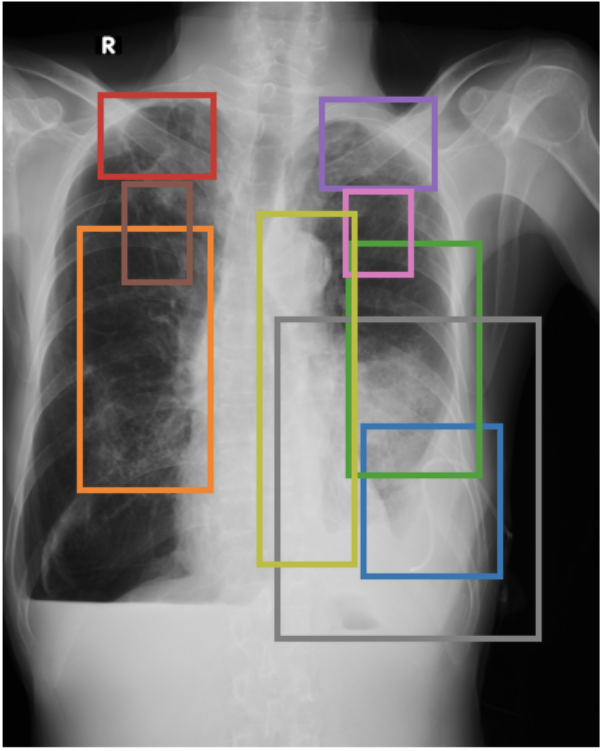

To address these drawbacks, state-of-the-art models such as MAIRA-2 [3] explicitly incorporate grounded report generation to better align local visual evidence with the textual findings. For example, MAIRA-2 is trained on a diverse set of localization-based tasks, including phrase grounding and grounded report generation. However, as shown in Figure 1, current models often exhibit a bias in which the target visual regions become overly associated with abnormal findings, leading to false positives in medical reports.

As shown in Table 1, our data composition reflects this imbalance: over 12.9M instances from Chest ImaGenome dominate the much smaller MS-CXR (815 PG instances) and PadChest-GR (12k instances) datasets. Beyond the imbalance between datasets, each dataset also exhibits substantial intra-dataset class imbalance. For example, anatomical regions in AGRG and semantic categories in PG are unevenly represented, leading the model to overfit frequent regions, neglect rare but clinically important ones, and hallucinate findings (Figure 1). Our curriculum framework addresses both sources of imbalance.

Figure 3 shows phrase grounding results for the phrase “Chronic inflammatory changes predominantly in both lung apices” on an image from PadChest-GR [11]. Both CURE and MAIRA-2 successfully identify the lung apices associated with the described findings. However, CURE’s localization is more accurate and better aligned with the phrase semantics, while MAIRA-2 provides a coarser prediction that only partially covers the relevant areas. As expected, MedGemma-4B-IT does not produce visual grounding outputs, and thus no bounding boxes are shown for this model.